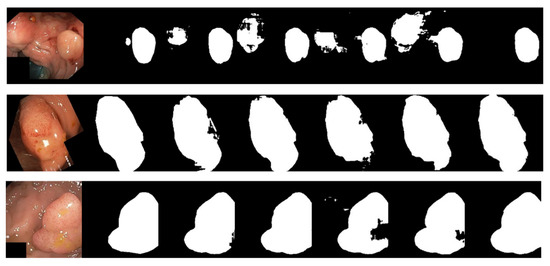

- Finally, we test and demonstrate the performance of LcmUNet on three medical image segmentation datasets: ISIC2018, BUSI, and Kvasir-SEG. Specifically, with only 1.49M parameters, we obtained segmentation accuracies of 85.19%, 63.99%, and 81.89% on the three datasets using a NVIDIA 3060 GPU, further highlighting the superiority of LcmUNet in the field of medical image segmentation.

4.2. Comparative Experiments

| Network | ISIC2018 | Kvasir-SEG | BUSI | |||||||||

| Iou | F1 | Re | Pr | Iou | F1 | Re | Pr | Iou | F1 | Re | Pr | |

| UNet | 80.17 | 88.71 | 86.61 | 91.50 | 76.20 | 86.13 | 85.82 | 87.55 | 52.12 | 67.80 | 65.21 | 76.36 |

| DeepLabv3+ | 82.07 | 89.70 | 89.01 | 91.61 | 79.15 | 88.04 | 88.40 | 88.57 | 58.72 | 73.16 | 72.00 | 78.44 |

| Fcn8s | 78.26 | 87.14 | 85.58 | 90.25 | 59.96 | 74.50 | 75.29 | 76.54 | 53.31 | 68.45 | 66.00 | 75.40 |

| SegNet | 79.93 | 87.55 | 90.56 | 88.34 | 79.33 | 88.20 | 86.55 | 90.62 | 58.85 | 73.37 | 72.21 | 75.99 |

| AttUNet | 80.92 | 89.20 | 88.48 | 90.45 | 78.48 | 88.55 | 87.01 | 89.13 | 56.30 | 71.34 | 67.84 | 77.14 |

| UNext | 82.00 | 89.87 | 88.98 | 91.29 | 77.57 | 86.99 | 87.67 | 88.05 | 60.74 | 75.35 | 77.05 | 75.46 |

| ResUnet | 77.86 | 87.27 | 86.30 | 88.34 | 67.10 | 79.93 | 78.55 | 83.02 | 44.23 | 60.79 | 57.15 | 73.25 |

| LcmUNet (Ours) | 85.19 | 91.81 | 92.07 | 92.99 | 81.89 | 89.92 | 88.93 | 91.79 | 63.99 | 77.37 | 79.96 | 76.69 |